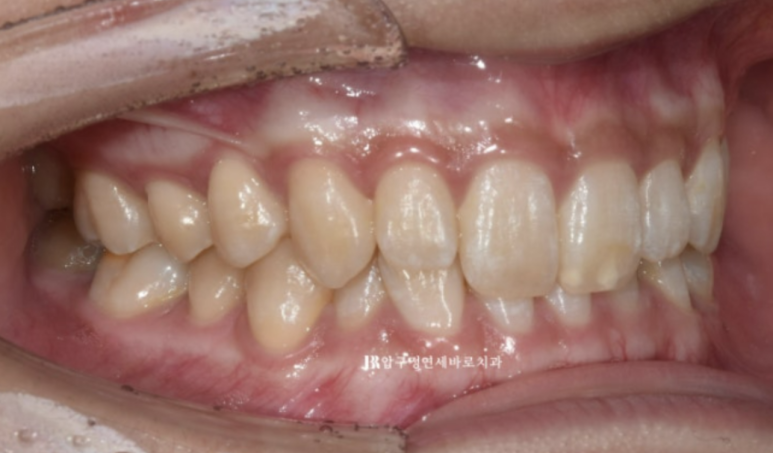

옥니를 고치고 싶어서 오신 분 입니다.

22.10

앞니가 깊게 물리는 과개교합이 보입니다.

앞니가 뒤로 기울어져 있으니 입술에 볼륨감이 부족하여 얇아 보입니다.